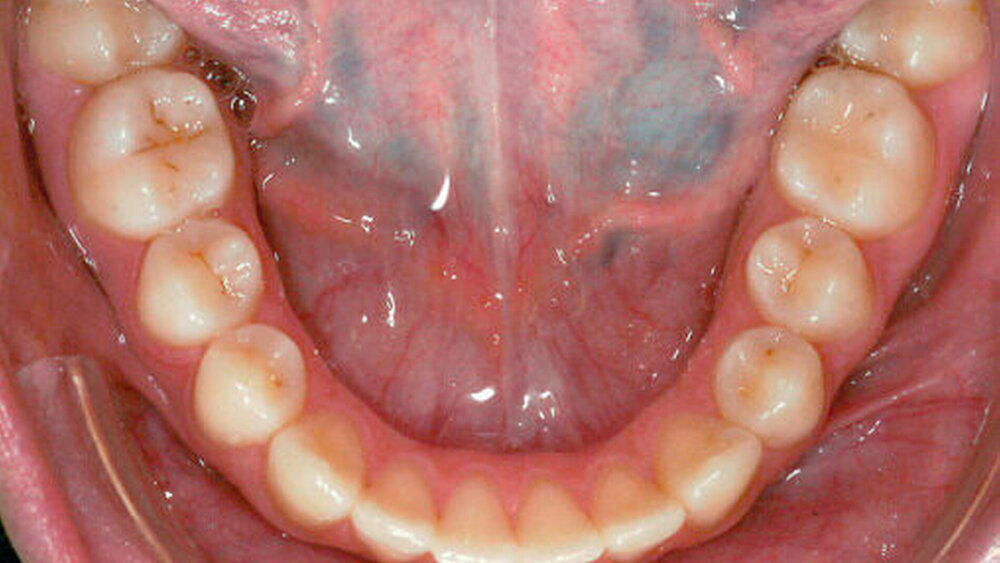

Die Patientin und deren Eltern wurden über die verschiedenen Versorgungsmöglichkeiten der Zähne 12 und 22 zur Rekonturierung und zur Verringerung der verbleibenden Lücken im Frontzahnbereich nach Abschluss der kieferorthopädischen Behandlung wie zum Beispiel direkte Kompositrestaurationen, Komposit- beziehungsweise Keramikveneers oder Frontzahnkronen, aufgeklärt. Da die Patientin ein kariesfreies Gebiss aufwies und möglichst Zahnhartsubstanz-schonend therapiert werden sollte, wurde eine Versorgung mit direkten Kompositrestaurationen gewählt. Aufgrund einer mangelnden Mundhygiene und einer daraus resultierenden plaqueinduzierten Gingivitis mit ausgeprägter Gingivahyperplasie (siehe Abbildung 2a) konnte ein adhäsiver Aufbau der seitlichen Schneidezähne und des Zahnes 23 erst nach der Entfernung der Multibracket-Apparatur und erfolgreicher Therapie der Gingivitis in Form von Mundhygienesitzungen und regelmäßigen Recalluntersuchungen erfolgen (siehe Abbildungen 2b und 2c). Es kann manchmal sinnvoller sein, den Aufbau bei in situ befindlicher Multibracket-Apparatur durchzuführen, um später noch etwaige Feinkorrekturen vornehmen zu können.